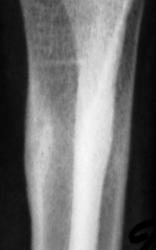

Определяются локальные оссифицированные периостальные наслоения в н/3 диафиза лучевой кости, что-то наподобие дефекта со склеротическим контуром по передней поверхности кости. У меня три варианта: 1 - консолидированный перелом лучевой кости; 2 - патологическая перестройка (читала у Рейнберга, может встречаться в лучевых и локтевых костях, выглядит как консолидированный перелом); 3 - первично-хр. остеомиелит.

Больше похоже на срастающийся перелом.

Но т равмы не было. Чем может быть вызвана "одностороняя реакция надкостницы"?

Считаю - это обычная перестойка трабекул костной ткани. Такие чаще всего я наблюдаю в дистальных отделах нижних конечностей, как вариант компенсации костной ткани на нагрузку.

Меня тоже смущает, и очень. Отправляйте к детским онкологам, пусть они контролируют. Основание: диафиз лучевой кости бульбообразно расширен ("поддут"), структура кости уплотнена муфтообразно/"пояском", менее выраженные, чем по переднему стенке кости, но аналогичные изменения отмечаются и по задней стенке диафиза, плюс периостальная реакция в прямой проекции.